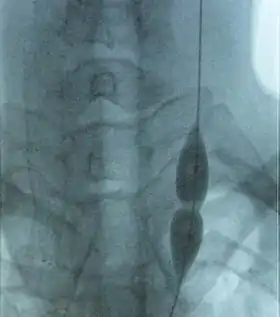

![]() توسيع بالبالون لوريد وداجي غائر متضيق (أخذت الصورة بواسطة مراقب تصوير الأوعية بالأشعة السينية). رغم أن الضغط في البالون منخفض نسبيا، فإن التضيق يمنع البالون من التوسع في الوسط. زيادة الضغط ستوسع مكان التضيق وتسمح للدم بالجريان. | |